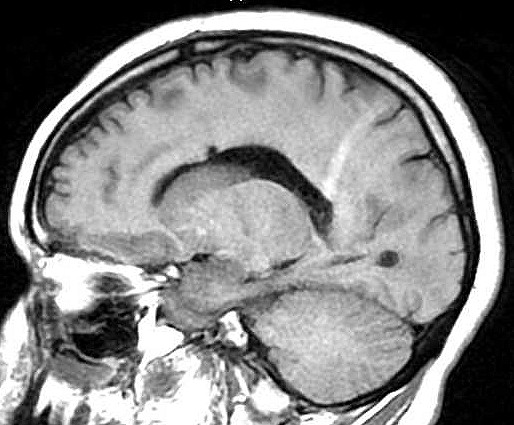

| Fem. 17a. |

| Nódulo sólido homogêneo preenchendo o III ventrículo, com limites precisos, com hipossinal em T1 e hipersinal em T2 e FLAIR, que se impregna por contraste paramagnético. Lesão menor implantada no assoalho do IV ventrículo provavelmente representa disseminação por via liquórica. |

| F. 17a. Tumor teratóide rabdóide atípico de III ventrículo. RM | HE | VIM, GFAP | HHF35, desmina, 1A4 | AE1AE3, EMA |